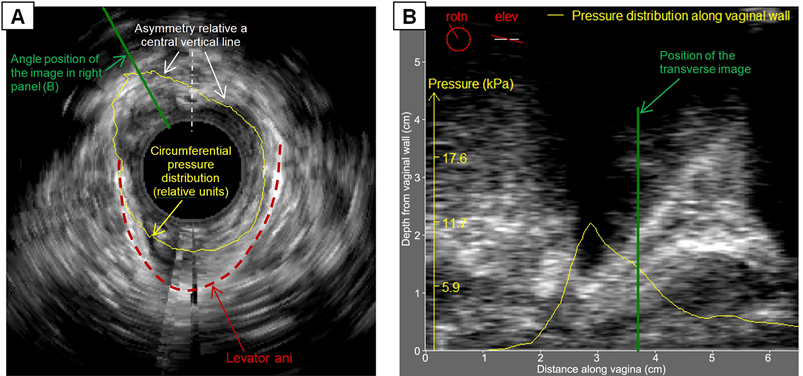

Test 3 (probe rotation by 360 degrees) allows acquisition of circumferential tactile and ultrasound images, which can be transformed into a 3D ultrasound image of the pelvic floor structures around the vagina. The angled tactile patterns from vaginal walls can be placed inside that 3D ultrasound image (see yellow pressure line in Figure 4(A)) to analyze suspicious findings with increased pressure feedback. Figure 4 presents an example of such images (orthogonal cross sections) with imposed pressure patterns. Mutual orthogonal positions for ultrasound images in Figure 4(A) and Figure 4(B) are marked by green lines. Asymmetry in the circumferential pressure distribution relative the vertical dashed line (see Figure 4(A)) reveals a nodule on the left side and levator ani defect on the right upper side; this patient has stage II anterior prolapse.

Figure 4. Orthogonal ultrasound images with pressure distribution patterns in Test 3 (probe rotation). (A) transverse image; (B) image along the vagina at specified angle for 53 y.o. patient with stage II anterior prolapse.